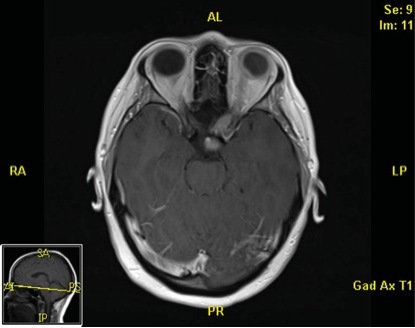

眼科检查示:左眼无光感(图 1),右眼视力 20/20。右眼眼底检查见视盘颞侧苍白(图 2),视野检查示左眼全盲,右眼颞侧偏盲(图 3)。右眼超声检查示视神经增粗,眼内回声增强(图 4)。头颅增强 MRI 示右侧视神经增粗并延伸至视交叉,侵犯垂体(图 5)。

图 5 头颅增强 MRI 示右侧视神经增粗并延伸至视交叉,侵犯垂体